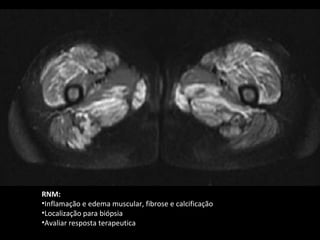

O documento discute Polimiosite e Dermatomiosite, doenças inflamatórias musculares. Apresenta os tipos de músculos e miopatias inflamatórias, quadro clínico, critérios diagnósticos, exames laboratoriais, tratamento e prognóstico. As principais informações são: a inflamação da musculatura estriada, os sinais e sintomas como fraqueza muscular e lesões de pele, os testes para detecção como dosagem de enzimas e biópsia muscular, e o tratamento com